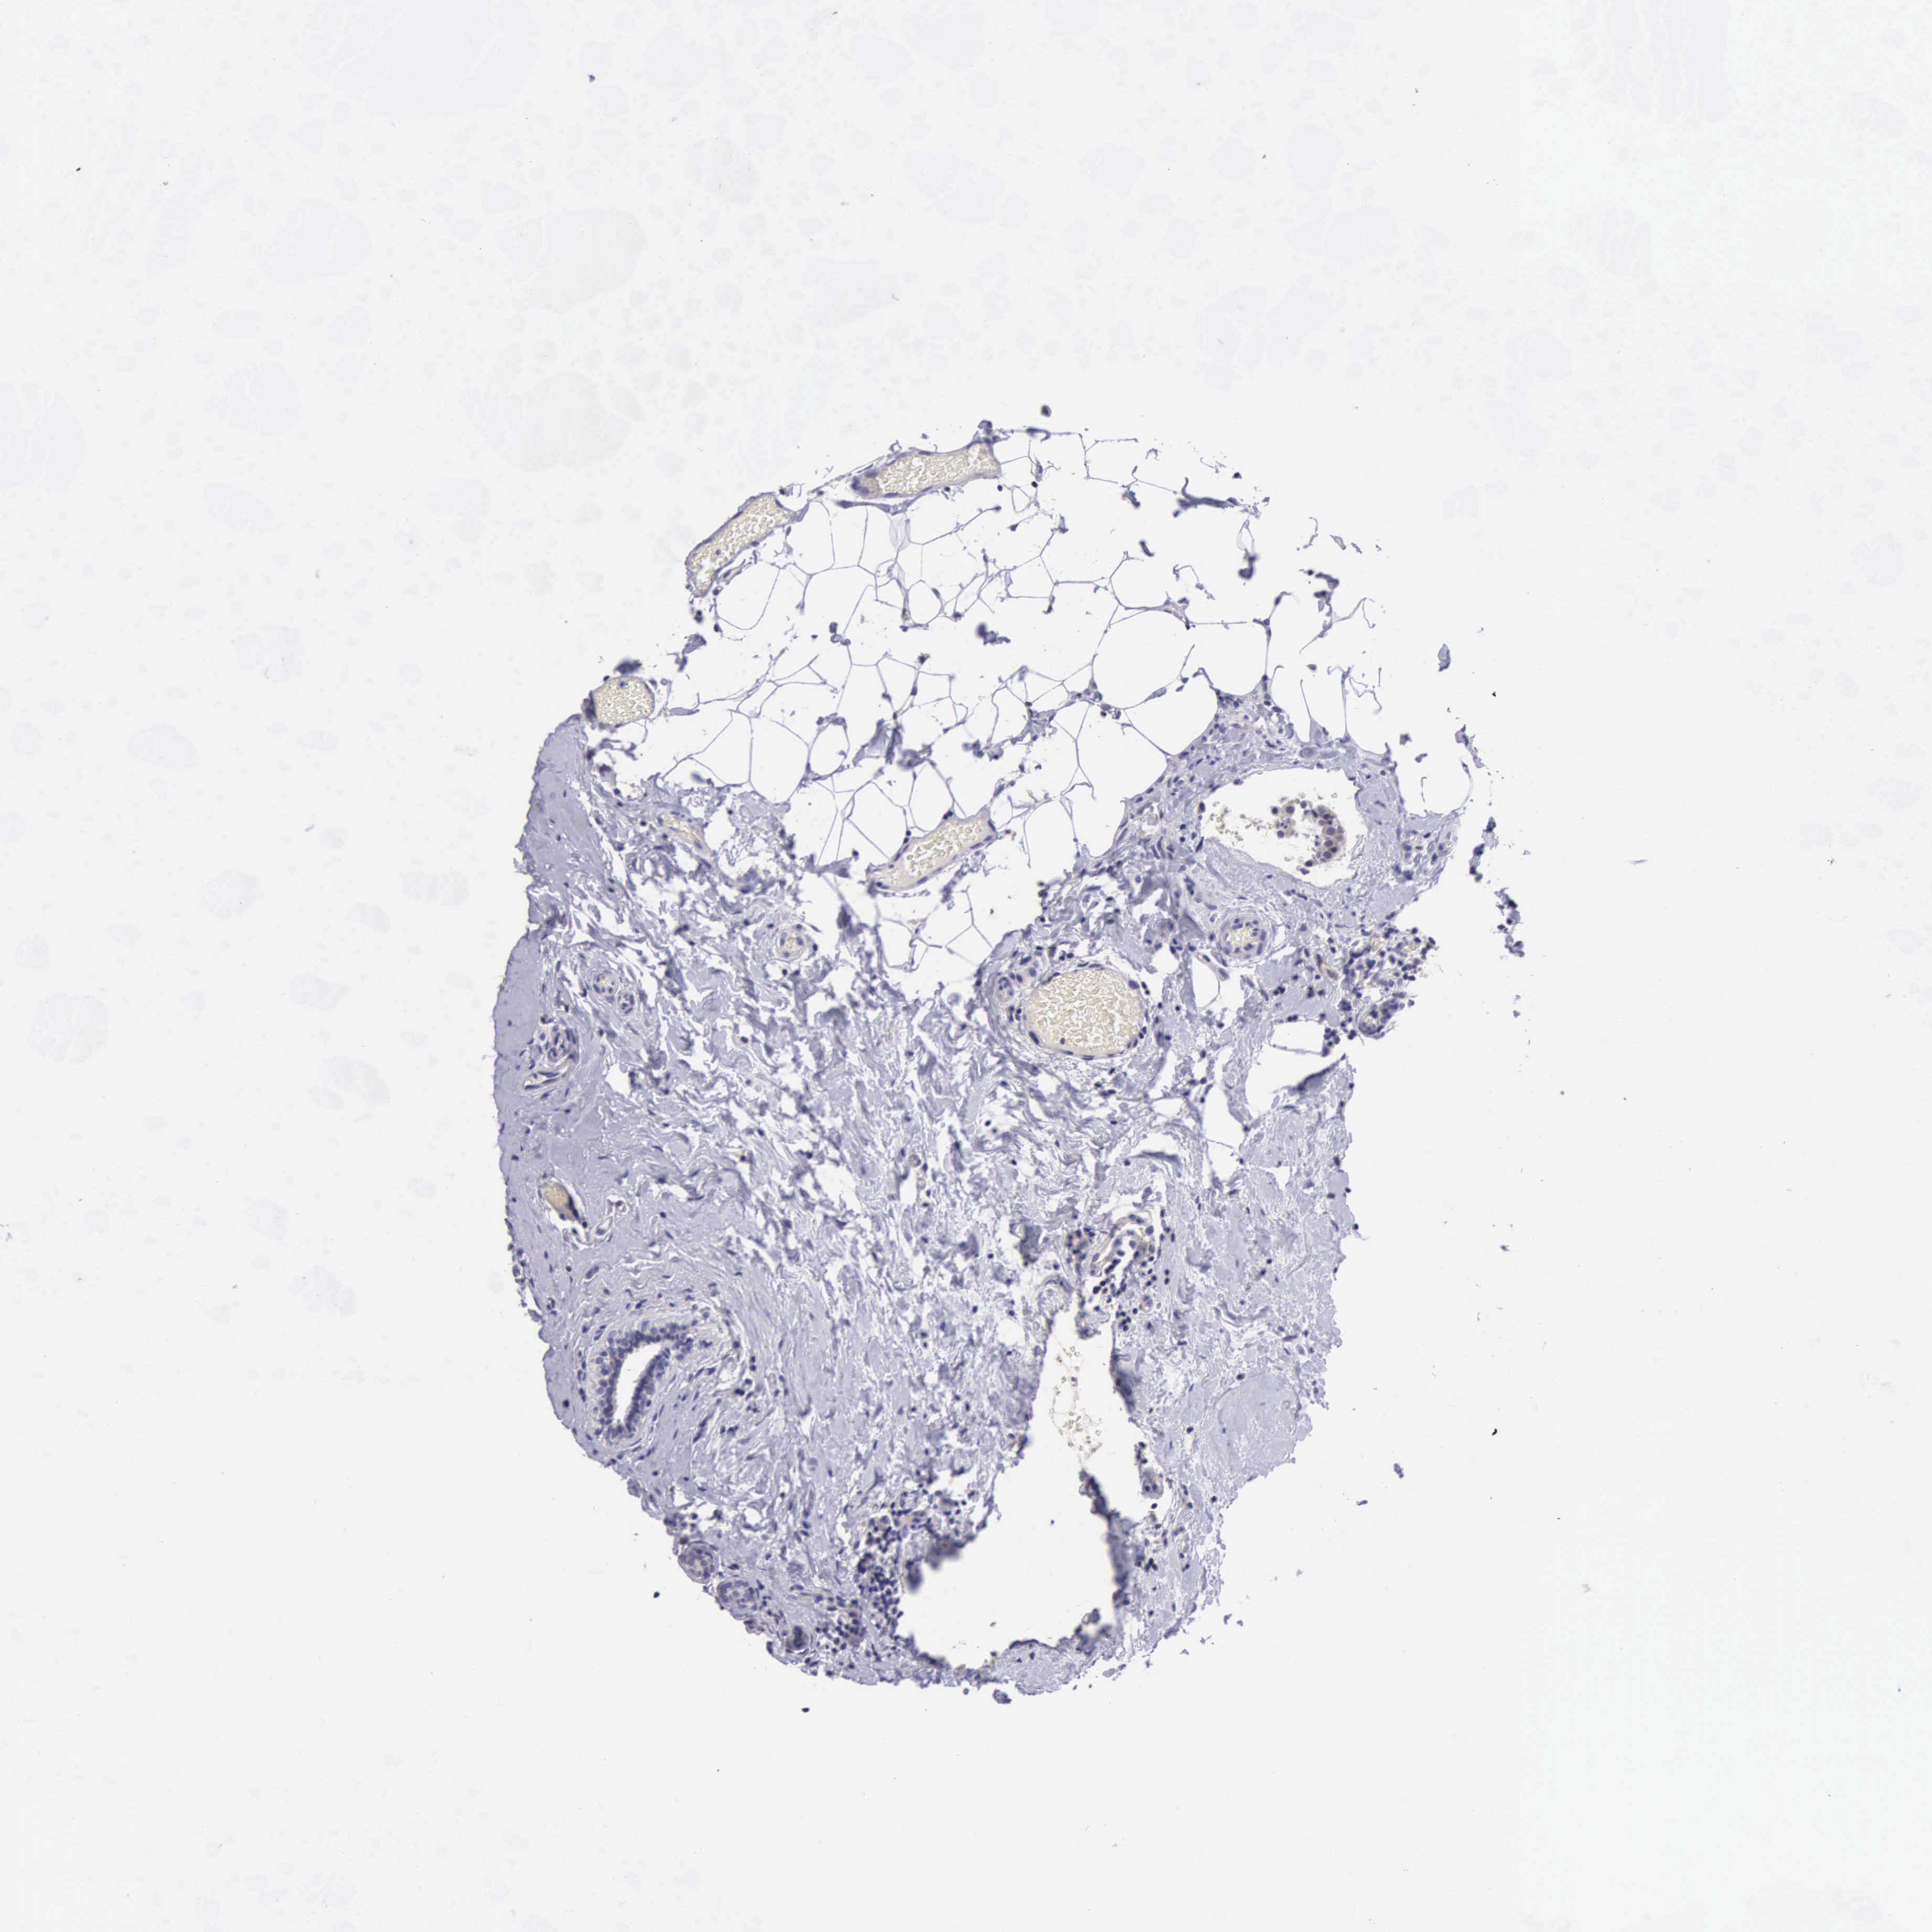

BRCA TCGA BRCA VALIDATION PROTEIN EXPRESSION

ANTIBODIES

AND

VALIDATION